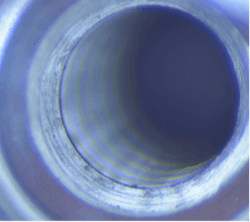

In total, seven out of seven samples yielded foreign material when swabbed (100%), resembling Ti particles and machine shavings. The particle size was estimated to be approximately 1–2 mm for larger shards (figures 3c and 3d) and around 20–30 microns for smaller particles (figure 4).